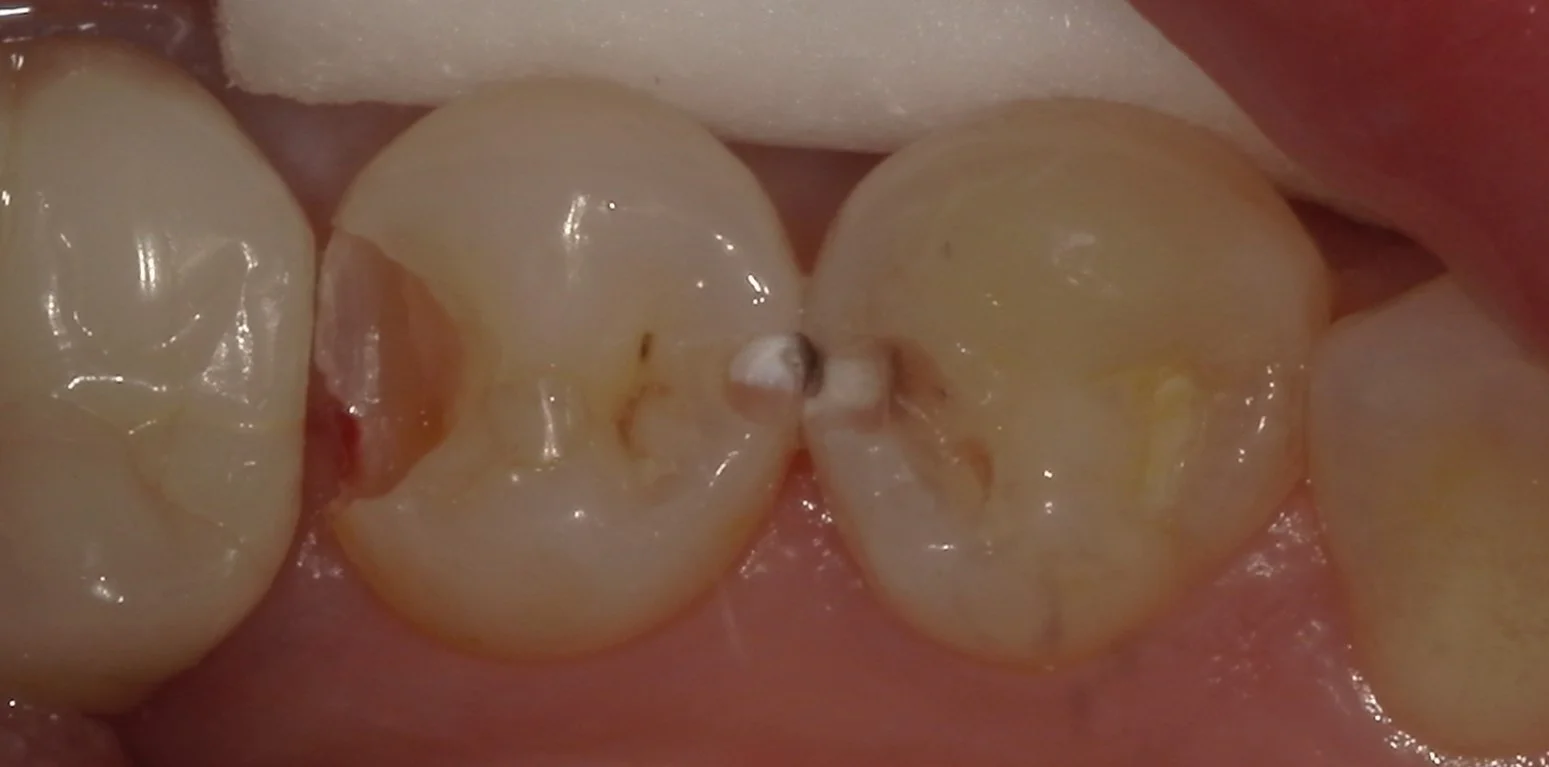

結構分かりづらいので、軽く削って分かりやすくしたのがこちらです。

歯の間の白い部分と黒い部分がある所が虫歯ですね。

あとは画面左側の茶色くなっているところ。これも虫歯です。